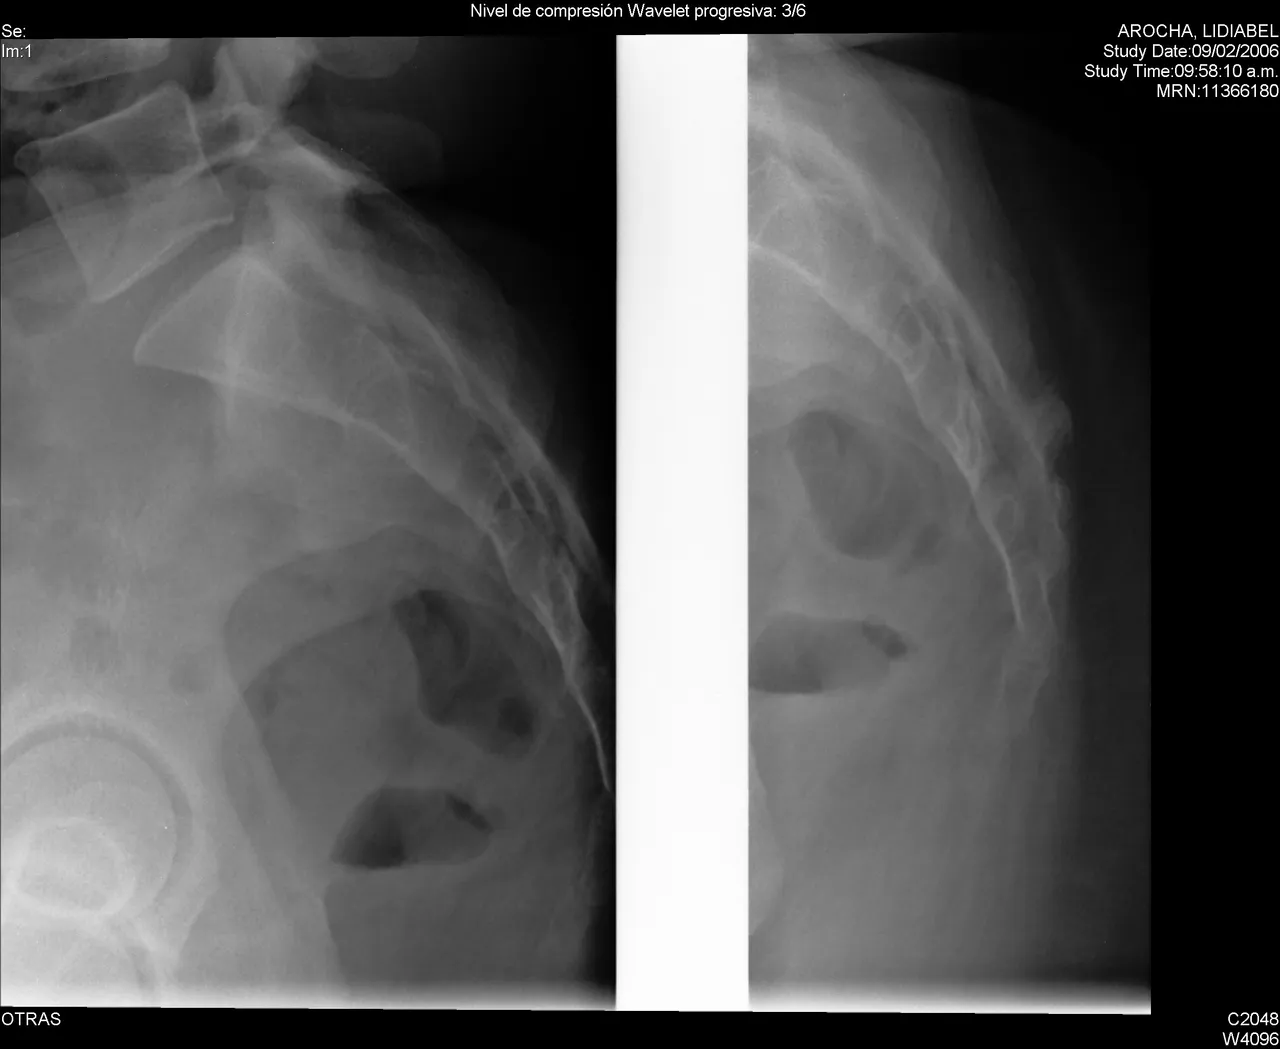

A spinal fracture (spinal compression fracture) occurs when one of the bones in the spine fractures or collapses.

These fractures occur most often in the fifth vertebra of the spine or lumbar spine, although they can also occur in the fourth lumbar vertebra. Fractures may occur on one or both sides of the pars bones. In more severe cases, spondylolisthesis may develop. This occurs when a fractured pars bone separates, allowing the injured vertebra to move forward.

Report any new or unusual back pain to your doctor right away. Early diagnosis can lead to more treatment options. A physical exam, along with an x-ray, can help determine whether or not you have a spinal fracture.